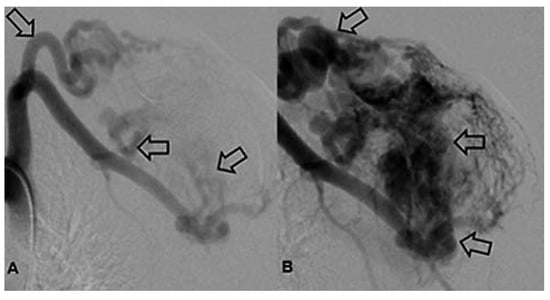

Case report A 22-year-old male experienced a presyncopal spell while studying for a university examination [...]